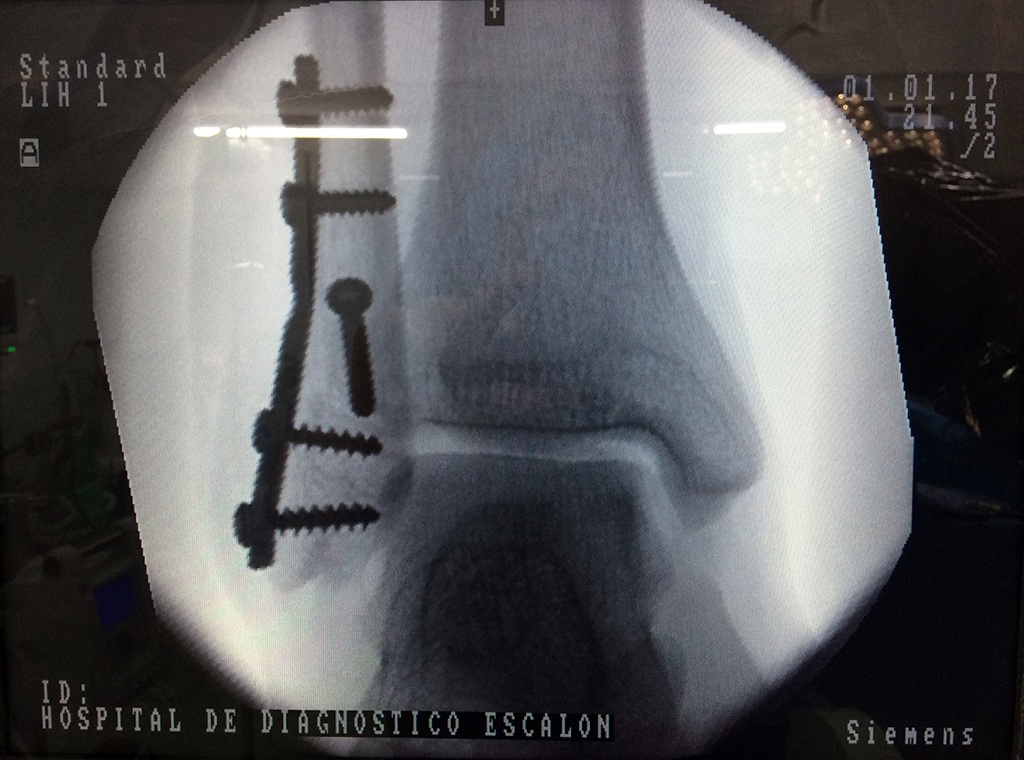

Una fractura de tobillo es la rotura de uno o más de los huesos del tobillo. Estas fracturas pueden ser:

Algunas fracturas de tobillo pueden requerir cirugía si:

- Los extremos de los huesos están desalineados entre sí (desplazados).

- La fractura se extiende hasta la articulación del tobillo (fractura intra-articular).

Cuando se necesita cirugía, es probable que esta implique el uso de clavijas de metal, tornillos o placas para sostener los huesos en su lugar mientras la fractura se consolida. Los elementos de soporte pueden ser temporales o permanentes.